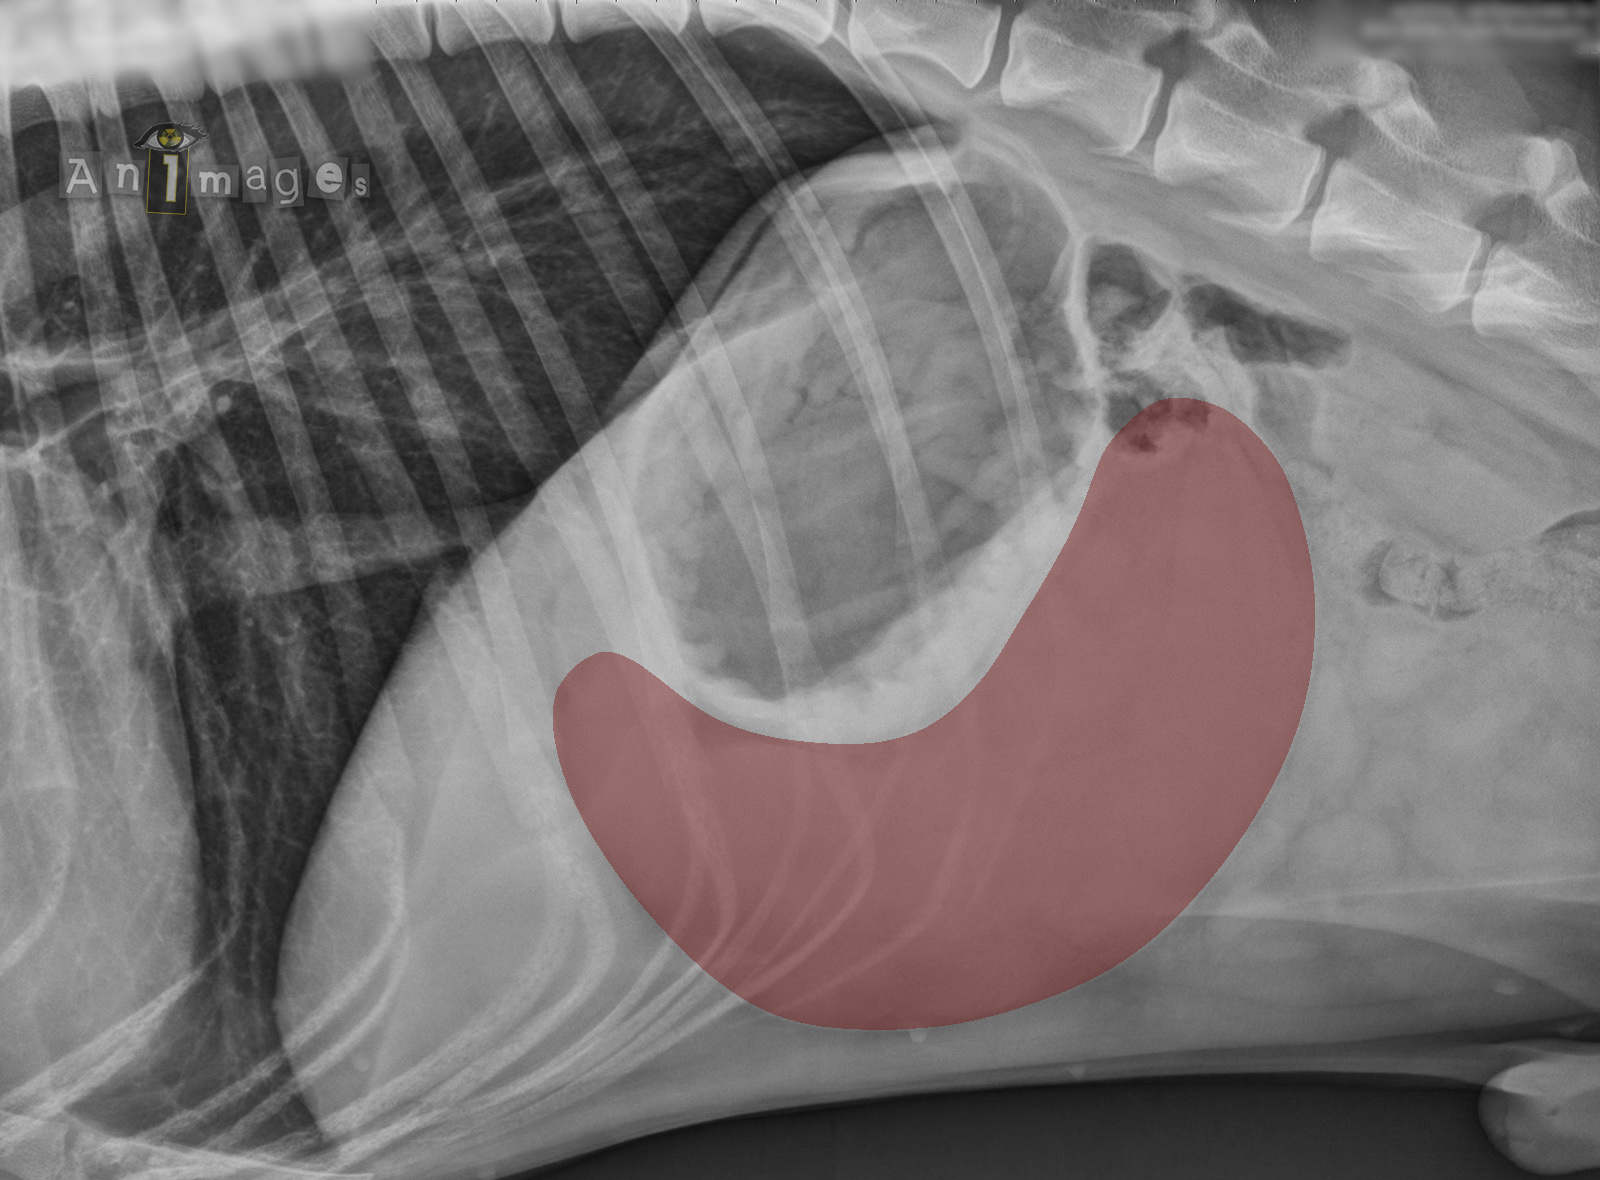

C inversé